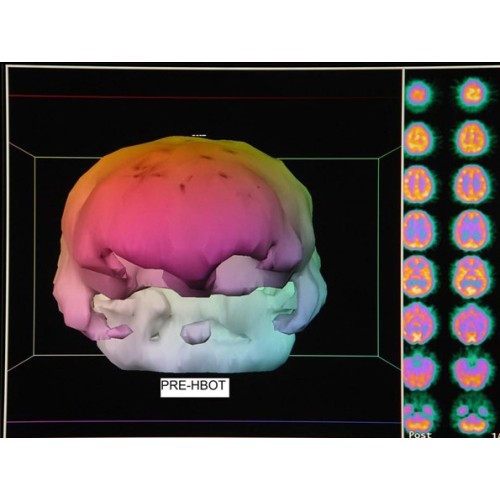

- Low pressure hyperbaric oxygen therapy and SPECT brain imaging in the treatment of blast-induced chronic traumatic brain injury (post-concussion syndrome) and post traumatic stress disorder: a case reportLow pressure hyperbaric oxygen therapy and SPECT brain imaging in the treatment of blast-induced chronic traumatic brain injury (post-concussion syndrome) and post traumatic stress disorder: a case reportNov 26,2024